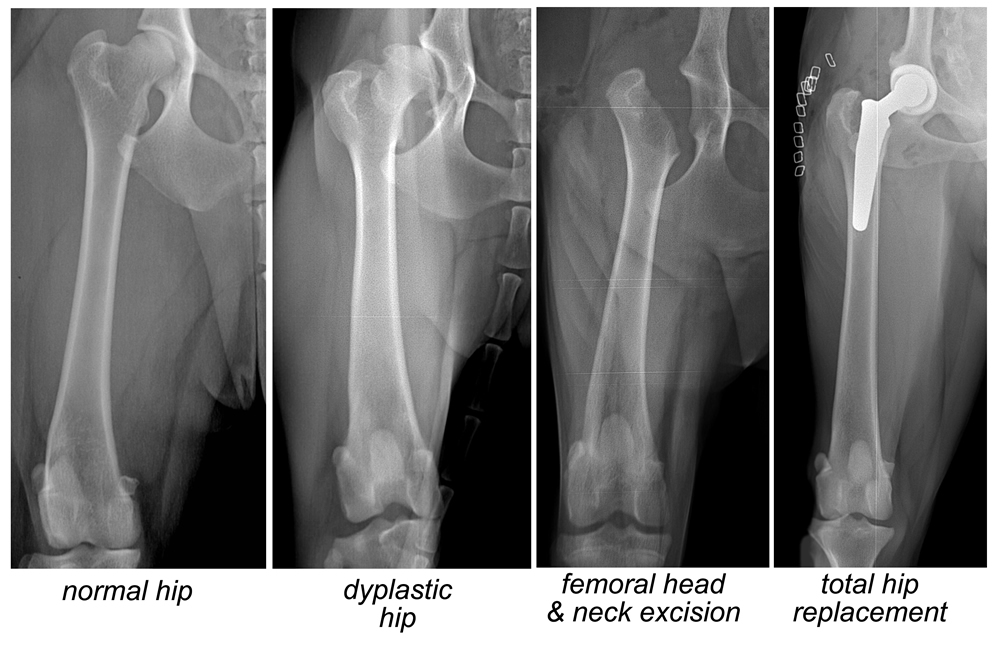

外科手術亦是其中一種治療方法。獸醫會根據狗狗的情況採用不同的手術。三處骨盆骨切開手術、全髖關節置換、股骨頭切除術。三處骨盆骨切開手術通常在少於12個月大、沒有患上退化性關節炎或症狀輕微的狗狗身上進行。全髖關節置換和股骨頭切除術通常在成年狗隻身上進行。